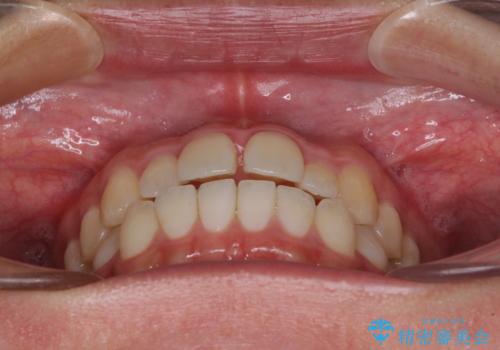

すきっ歯とオープンバイトをインビザラインで改善

- 前歯の上下スペースと前歯の隙間を気にして来院された患者様です。

インビザラインにより上下の前歯の隙間を閉じていくこととしました。

上下の隙間に舌が入り込むことが、すきっ歯やオープンバイトの原因であったため、舌の筋肉のトレーニングも並行して行い、後戻りの抑制を図りました。